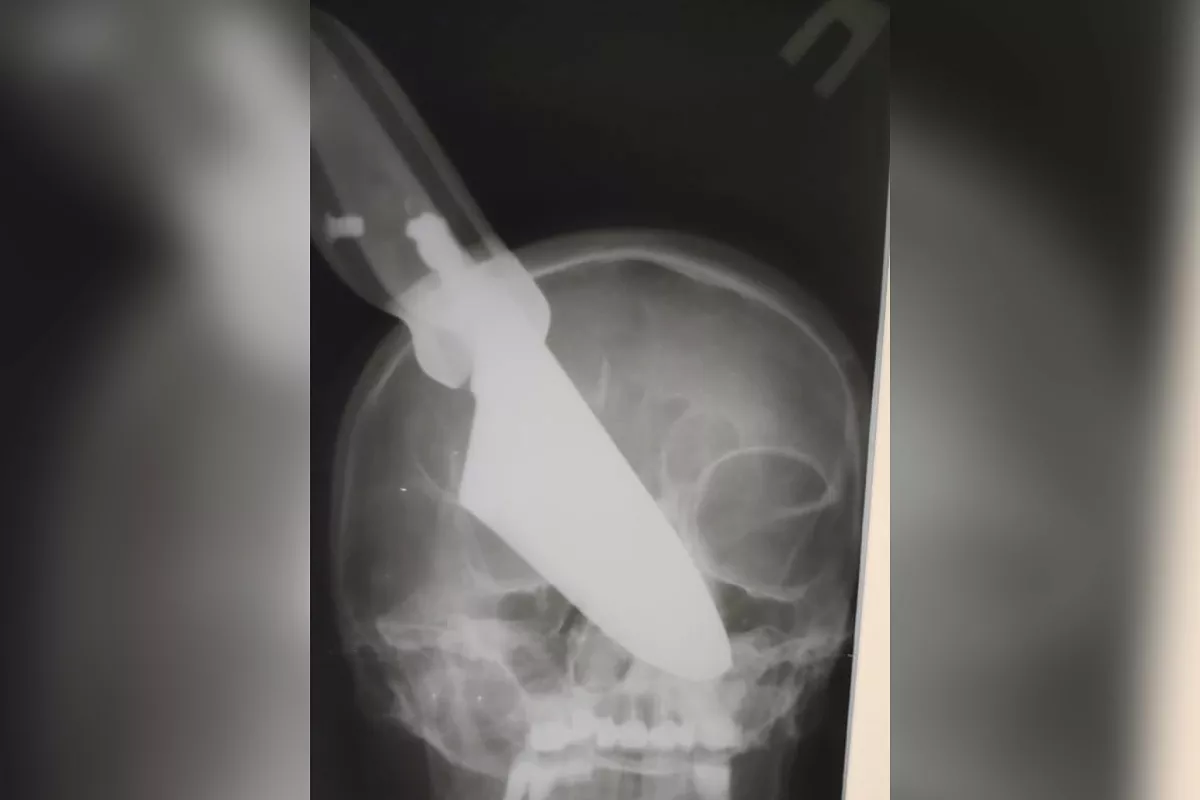

В Апшеронске врачи достали 25-сантиметровый нож из головы женщины

В больницу местная жительница попала после ссоры с мужем.

Врачи Апшеронской ЦРБ извлекли из головы пациентки нож длиной 25 см. Перед тем, как достать холодное оружие, женщине сделали рентген. Лезвие вошло в голову в районе носа. До извлечения холодного оружия до конца врачи не понимали масштаб повреждений. Операция длилась больше часа.

- Повреждены были носовая перегородка, левые носовые раковины, левая гайморовая пазуха. В настоящее время пациентка чувствует себя удовлетворительно. В последующем ей предстоит ряд плановых операций, - рассказали «Кубанским новостям» в пресс-службе министерства здравоохранения Краснодарского края.

После того, как женщина восстановится от операции, которая спасли ей жизнь, пациентке предстоит пройти через ряд хирургических действий по реконструкции внешности.